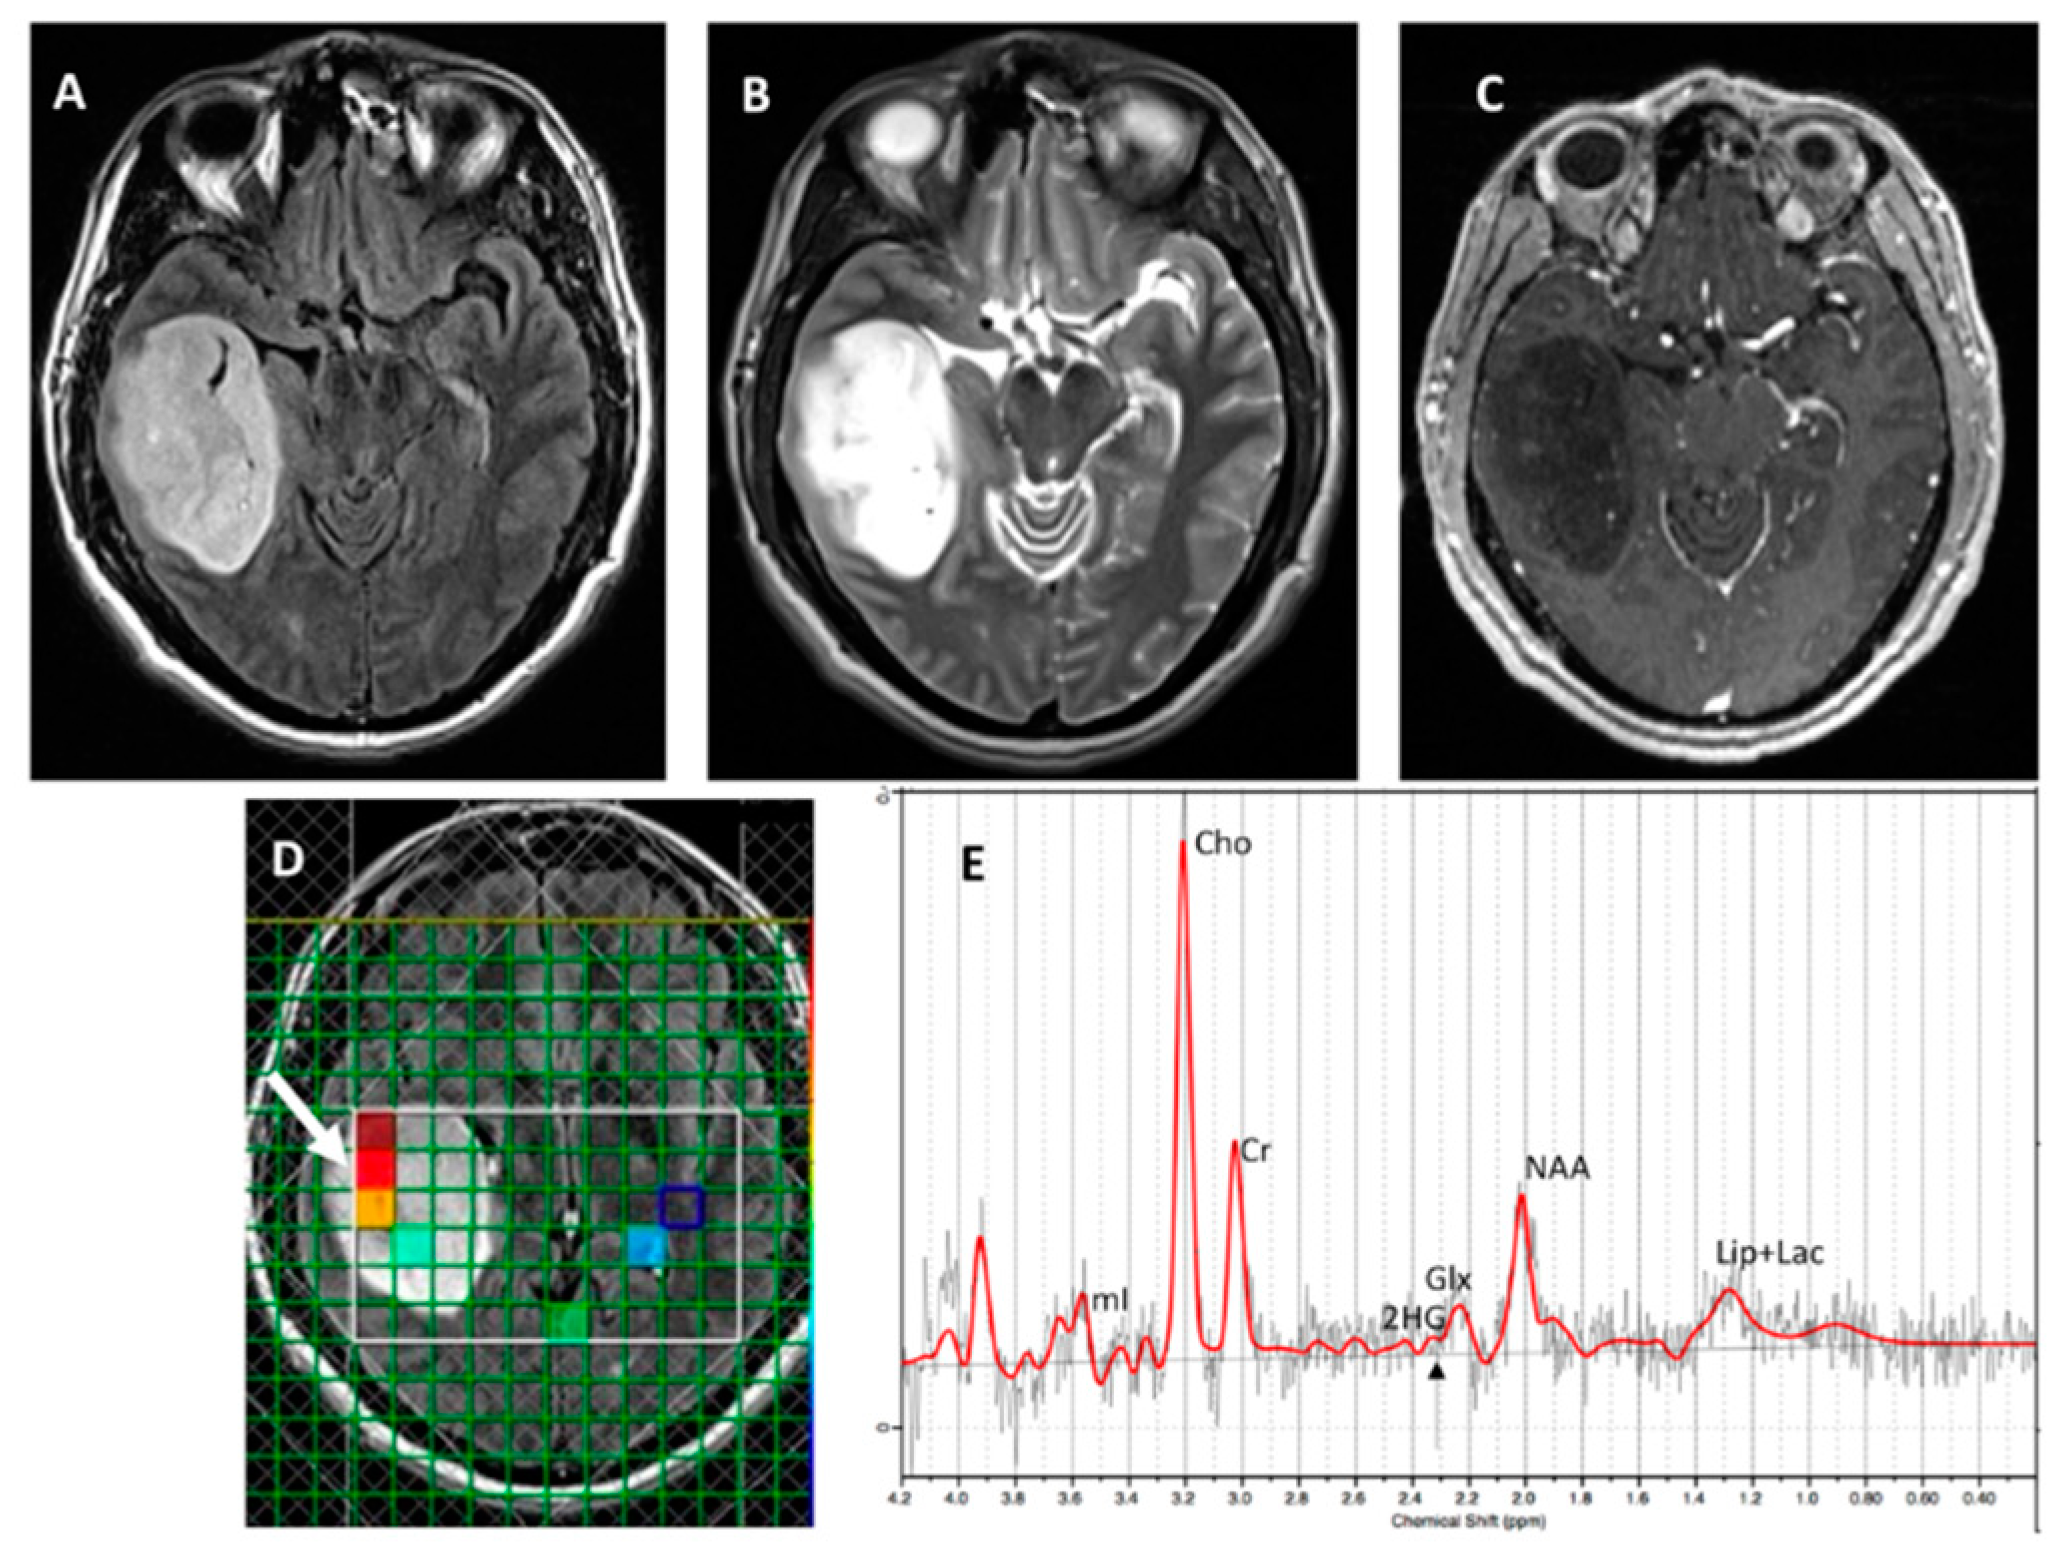

Figure 3. A glioma patient, status post resection. (A) T2-FLAIR and (B) T2-W images demonstrate expansile signal abnormality lateral to resection cavity in the right frontal lobe. (C) Post-contrast T1 image shows no abnormal enhancement. (D) SVS demonstrates elevated Cho/Cr (0.37; CRLB=6%) and metabolic levels of 2HG (2HG/Cr =0.4; CRLB=33%; black arrow). (E) Histopathological and (F) immunohistochemical analyses were consistent with grade-3 oligodendroglioma, 1p19q co-deletion with positive IDH1 mutational status.